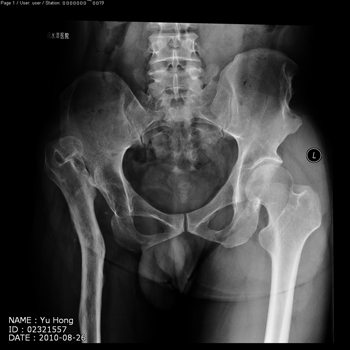

total hip replacement on hips with unilateral severe dysplasia and high riding